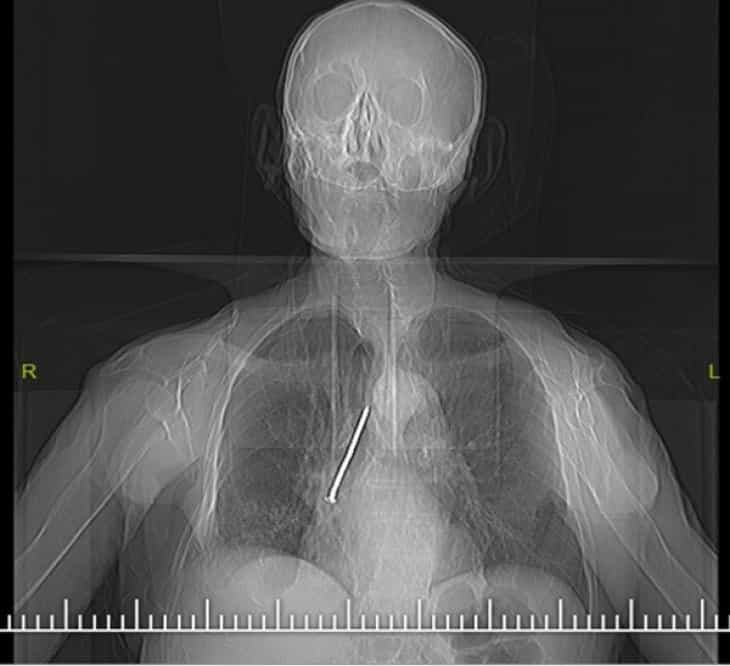

Elazığ Fethi Sekin Şehir Hastanesine öksürük ve nefes darlığı şikayetiyle başvuran 91 yaşındaki Keko Ateş'in röntgeninde, göğsünde 10 santimetrelik çivi olduğu ortaya çıktı.

Ateş'in soluk borusundan sağ akciğerine kaçmış olan çivi "Rijit bronkoskopi" adı verilen işlemle çıkartıldı.

Kılıç, "Larenks kanseri nedeniyle 24 yıl önce boynundan nefes borusuna açılan açıklık aracılığıyla nefes alıp verebilen hasta, nefes borusundaki bu açıklığı temizlemek amacıyla kullandığı 10 santimlik çiviyi soluk borusuna kaçırmış. Bu nedenle gelişen öksürük ve nefes darlığı şikayeti ile önce başka bir sağlık merkezine başvurmuş, ardından Fethi Sekin Şehir Hastanemiz Göğüs Cerrahisi Kliniğine yönlendirilmiş. Biz de hastanede 91 yaşındaki hastamıza çektiğimiz filmde soluk borusu içerisinde, sağ akciğer içerisine doğru kaçmış olan çiviyi tespit ettik. Uyguladığımız Rijit bronskoskopi işlemi ile nefes borusundaki 10 santimetrelik çiviyi başarılı bir şekilde çıkardık. Hastamızı ameliyat sonrası bir süre serviste takip ettikten sonra gün içerisinde taburcu ettik. Nadir de olsa bu tarz durumlarla karşılaşıyoruz. Bu tür durumlarda hızlı müdahale etmek oldukça önemli.” dedi.